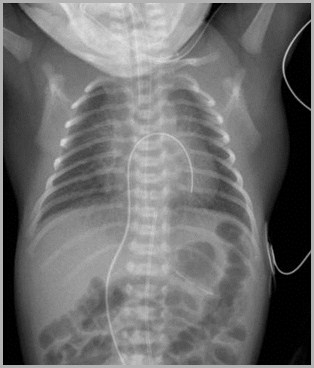

UAC too high (T5)Umbilical Venous Catheter too low over liver

5

11